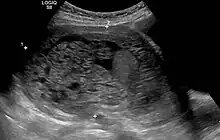

The diagnosis is strongly suggested by ultrasound (sonogram), but definitive diagnosis requires histopathological examination. On ultrasound, the mole resembles a bunch of grapes ("cluster of grapes" or "honeycombed uterus" or "snow-storm").[14] There is increased trophoblast proliferation and enlarging of the chorionic villi, and angiogenesis in the trophoblasts is impaired.[15]

Transvaginal ultrasonography showing a molar pregnancy.

Molar pregnancy in ultrasound